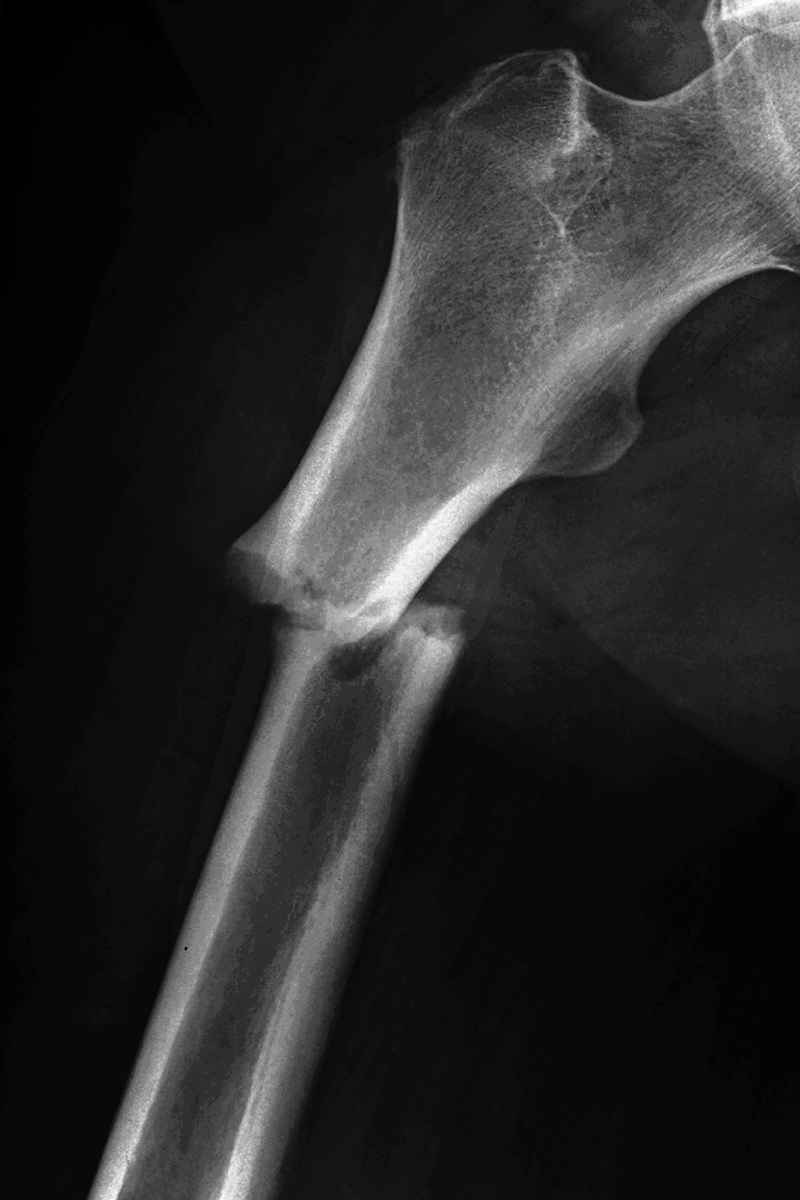

Su trabajo gira en torno a su propia vida, utiliza su obra como herramienta de búsqueda personal.

Trabaja con imágenes cotidianas que captura de forma inconsciente, creando de esta forma un mapa visual basado en experiencias personales, y que luego le sirven de base para reflexionar sobre su propia identidad.